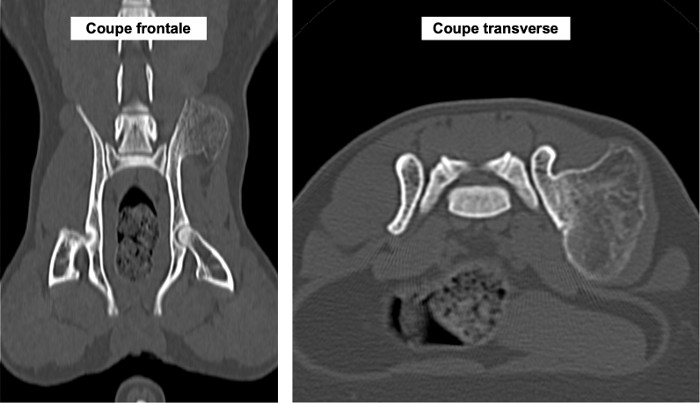

Nous présentons également un cas d'extension d'une rhino-sinusite infectieuse chez un chat présentant une ataxie. Un scanner montre des lésions naso-sinusales agressives avec lyse de la paroi sinusale frontale et empyème méningé adjacent. Une trépanation du sinus frontal permet de réaliser des prélèvements pour analyses bactériologiques et mycologiques. Un traitement antibiotique ciblé permet une bonne évolution clinique.